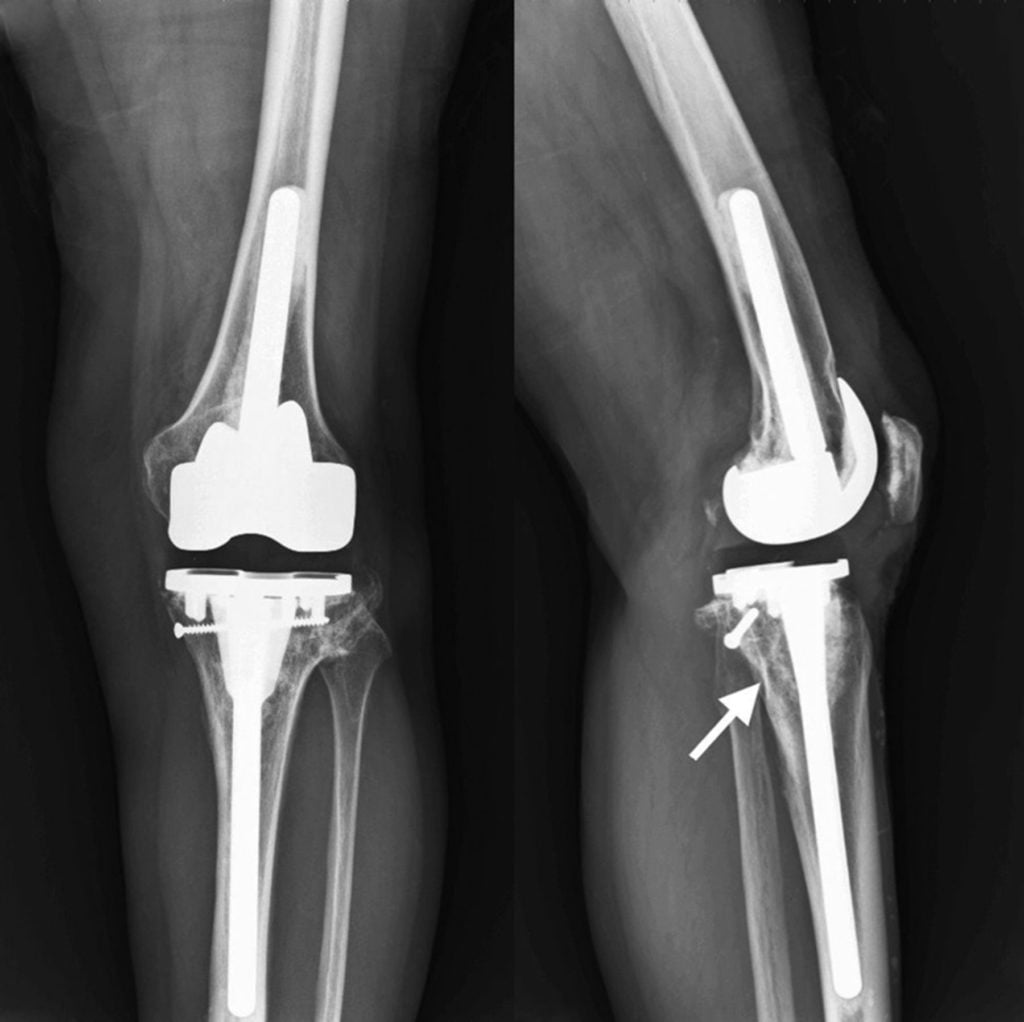

Тип фиксации

В хирургии используется два основных метода, обеспечивающих фиксацию имплантата с костями, позволяя им двигаться, как единое целое:

- цементный. На эндопротезе есть поверхность, на которую накладывается специальный костный цемент для надежного сцепления с костями. Соединение успешно используется для всех типов замены коленного сустава. У некоторых молодых и более активных пациентов наблюдались проблемы ослабления цементного состава, однако этот материал в последнее время доработан и улучшен;

- бесцементный. Имплантаты имеют специальную текстурированную, пористую поверхность, через которую костная масса свободно прорастает во внутреннюю полость эндопротеза. Винты и штифты стабилизируют соединение, пока не произошло врастание. При установке приспособления требуется более длительный период восстановления. Не применяются для пациентов с остеопорозом, поскольку врастающая кость должна быть в хорошем состоянии.

Некоторыми хирургами используется гибридный метод с элементами обоих типов фиксации, однако он применяется при тазобедренном эндопротезировании.